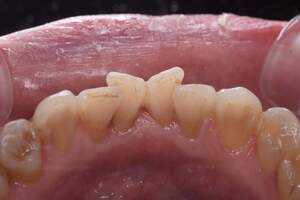

歯石除去

治療前

治療後

| 年齢 | 25歳・男性 |

| 主訴 | 歯石をとりたい・検診 |

| 治療内容 | 各種検査・歯石除去 |

| 治療期間 | 60分 |

| 費用 | 初診料3,000〜4,000円前後 +歯石除去約1,000円 |

| リスク・副作用 | ・処置後に歯がしみることがあります。 ・歯と歯の間に隙間ができるので、息が漏れ発音しにくいと感じることがあります。 ・歯ぐきの炎症が軽減すると歯ぐきが引き締まり、歯が長く見えることがあります。 |

| 担当者所見 | 前歯の裏側にすぐに歯石が溜まってしまいザラザラして気になるとご相談いただいたので適切な歯ブラシの当て方とフロスの通し方をお伝えさせて頂きました。 |